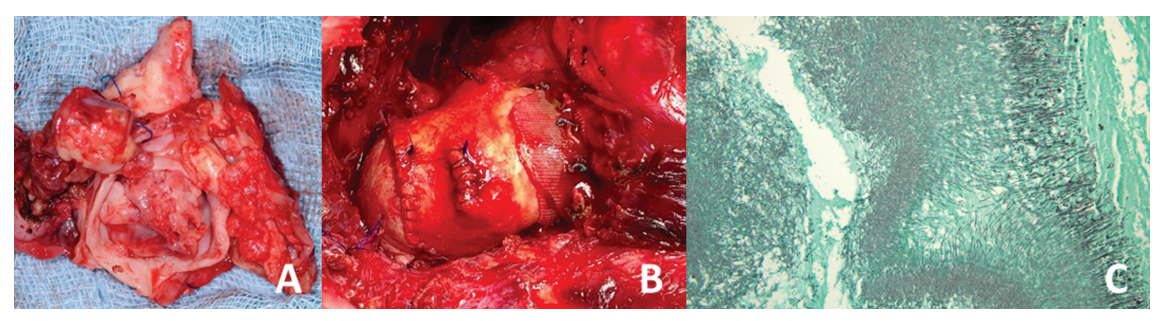

由于严重的肺阻塞和可能的脓毒性栓塞,安排了紧急手术。通过右锁骨下动脉和左股动脉建立动脉插管。两条动脉都显示出小的管腔,单独使用一条动脉无法提供足够的旁路流量。出于同样的原因,两条动脉都不适合直接插管。因此,需要两个 7mm的镀银假体进行动脉连接。通过左股静脉和右颈静脉进行经皮静脉插管。后者是必要 的,因为上腔静脉完全血栓形成,而且不可能单独通过股静脉插管进行上腔静脉引流。体外循环(CPB)连接如图所示(图2)。降温至 30℃再入胸腔后,发现胸骨柄附着6× 7 cm炎性肿块。脓肿腔打开,显露同种移植物坏死。假体前壁因感染坏死。一个1.3×3cm 的血栓完全阻塞了同种移植物瓣膜。脓毒性血栓延伸至右肺动脉。小心地取出同种移植物血栓,用吸盘取右肺动脉局部血栓。离体组织如图所示(图3A)。手术清创后,用KerraSol (Crawford Healthcare GmbH, Valley, 德国)冲洗伤口。在RVOT植入25mm的Medtronic plc.Freestyle根部生物瓣膜(Medtronic plc., 都柏林,爱尔兰) (图3 B)。

采用牛心包补片建立腹侧吻合。整个手术是在心脏跳动的状态下进行的。同种移植物的组织学表现为活动性和慢性肉芽肿性炎症,并伴有广泛的真菌定植(图3C)。微生物学分析显示,离体组织中有白色念珠菌。

图3. (A)外植同种移植物和脓毒性血栓。(B)重建的右心室流出道(外科医生的视角)。(C)移除组织内的真菌定植(Grocott染色,放大约10倍)。